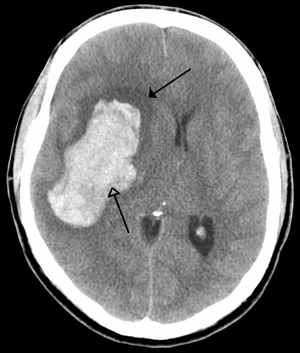

CT scan slice of the brain showing a right-hemispheric ischemic stroke (الجانب الأيسر من الصورة). | |

السكتة أو الجلطة الدماغية STROKE هي تأذي عصبي يحدث عندما يتوقف جريان الدم وتغذيته في منطقة من مناطق الدماغ نتيجة جلطة أو خثرة دموية. ويطلق نفس الاسم أيضا على متلازمة ضياع مفاجيء في الوظائف العصبونية نتيجة اضطراب في الجريان الدموي الدماغي غالبا ما يكون في شرايين الدماغ وأحيانا يكون في أوردة الدماغ.

جزء الدماغ الذي يحدث به الاضطراب الدوراني ونقص التغذية الدموية يعاني بالتالي من نقص في الأكسجين الوارد مع الدم، مما يؤدي لتضرر و موت الخلايا العصبية في هذا الجزء مؤثرا على وظيفة هذا الجزء من الدماغ.